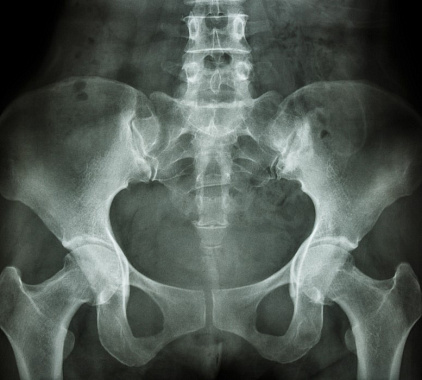

Расшифровку полученных рентгенограмм производит врач-рентгенолог в течение 2-3 часов после исследования. Пациент получает на руки не только подробный протокол с описанием обнаруженных патологий, но и снимки – распечатки и в цифровом формате. Заболевания проявляются на визуализациях зонами с повышенной эхогенностью, либо же участками с затемнениями и помутнениями. Наибольшее внимание на рентгене таза врач уделяет следующим моментам:

- Верхние и нижние ветви лонных костей не имеют смещений, положение соответствует анатомической норме;

- Состояние головок бедренных костей – наблюдается конгруэнтность в соответствии с вертлужными впадинами, не идентифицируется краевых костных заострений, остеопороза, опухолей;

- Суставные щели имеют размер в соответствии с нормой, что говорит о нормальном состоянии межкостных хрящей;

- Параартикулярные ткани не имеют зон с повышенной эхогенностью (новообразований), допускается наличие единичных флеболитов в полости малого таза.

При анализе полученных изображений важно учитывать индивидуальный анамнез пациента, историю болезни, а также наличие у него хронических заболеваний. В некоторых случаях показания нормы могут варьироваться.